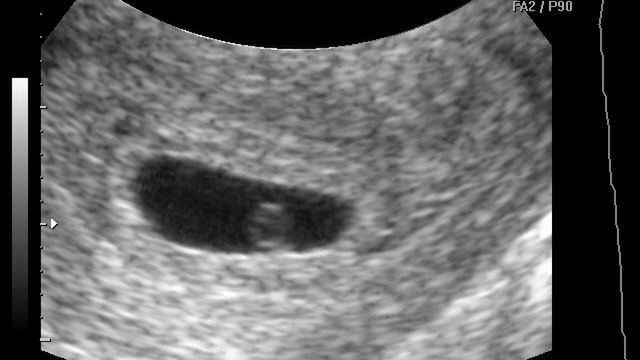

Płód w 5 tygodniu ciąży

/ 1Płód w 5 tygodniu ciąży - długość płodu

Pod koniec 5-go tygodnia dziecko będzie miało ok. 2 mm